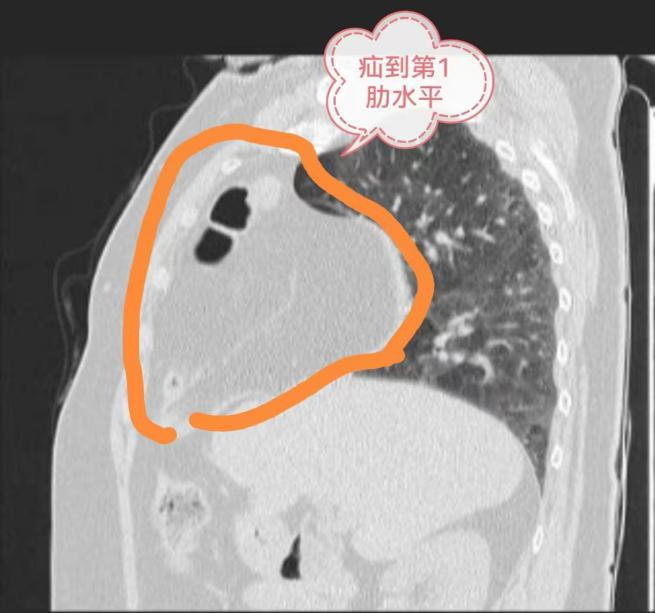

在我们体内,有许多看似平凡却至关重要的器官,它们默默合作,保障我们的生命活动能够持续且稳定地进行。其中,膈肌就是这样一个不可或缺的角色,它如同一道屏障,将胸腔和腹腔分隔开来,同时也参与呼吸的过程。然而,当膈肌出现问题时,一种名为膈疝的疾病就可能悄然发生,给我们的生活和工作带来诸多困扰,甚至威胁到我们的生命。 8年前 患者刘奶奶被当地医院 诊断为“冠心病” 一直口服药物治疗 效果不明显 近日,刘奶奶(75岁)来到贵州航天医院做了胸部CT、冠脉造影等检查,经过心血管内科、呼吸与危重症医学科、心胸外科、影像科等多学科会诊讨论,确诊并没有冠心病,而是因为有“膈疝”导致她的一系列症状。而且,刘奶奶的膈疝还非常严重,腹部的肠管和网膜已经“跑”到右侧胸腔顶部去了,还占据了整个右侧前胸腔,难怪会出现那么明显的症状。通常这类严重的膈疝多采用开放手术,需要至少15厘米长的切口。 贵州航天医院心胸外科陈光春主任团队经过精心术前准备,为刘奶奶行胸腔镜下微创膈疝修补术,仅仅在胸壁打了4个0.5-1.0cm小孔,就成功将“疝”移到右侧胸腔的肠管和网膜等腹腔内容物送回了腹腔,并将膈肌缺损的部位缝合加固,手术圆满成功。术后4天,刘奶奶各项指征恢复正常出院,她发现之前那些活动后胸闷、心悸、气促、呼吸困难等症状都消失了,一口气能走上四五楼都毫无压力。 刘奶奶的这个症状在术后得到缓解了,她感叹“这个手术过程,仅仅在胸部打了几个小“洞洞”就完成了,术后恢复还这么快!感谢航天医院的精心诊治!” 科 普 什么是隔疝? 日常说的“疝气”,一般是指在腹部体表有异常包块,用手按压的时候包块可以进入腹腔,认为包块内有气,所以称为疝气。 其实,疝是指人体内脏器或组织离开其正常位置跑到了另一地方,疝不仅会出现在体表。比如:腹腔脏器还会通过和胸腔之间的膈肌薄弱部位到达胸腔,称之为“膈疝”,此时往往因为压迫心肺而出现心悸、气促、呼吸困难、胸痛等症状而容易被误诊为心脏病或肺病。 治疗隔疝 手术是最佳治疗方法 膈疝的手术治疗方法主要包括膈疝修补术。对于先天性膈疝,如果临床无明显症状,可以等到患者年龄稍大后再进行手术治疗。 但如果出现肠梗阻或幽门梗阻等症状,或者出现心、肺压迫症状,如心悸、气促、咳嗽、胸闷、呼吸困难、发绀等,不论年龄大小都应尽早进行手术治疗。 术后注意事项 膈疝手术后的患者,在饮食方面,应遵循少食多餐、细嚼慢咽的原则,避免暴饮暴食和进食过快。同时,应选择易消化、营养丰富的食物,避免进食辛辣、油腻等刺激性食物,以免给刚刚修复的膈肌带来额外的负担。 在休息方面,患者应保持充足的睡眠和休息,避免过度劳累和剧烈运动。适度的活动可以促进血液循环和新陈代谢,有助于身体的康复,但过度活动则可能导致伤口裂开或复发。 此外,术后患者还需定期进行复查和随访,以及时发现并处理可能出现的并发症或复发情况。医生会根据患者的具体情况制定个性化的康复计划,帮助患者尽快恢复健康。 贵州航天医院心胸外科简介 心胸外科是诊治疾病种类较为复杂,专科性非常强的一门学科。心胸外科手术难度大,风险高,对设备和配套要求也高,大众对心胸外科经常会存有误解,误认为心胸外科只是看胸外面的病,这就很容易让人联想到乳腺疾病等,其实胸外科主要看的是胸腔内的病,主要是食管、气管及肺上的疾病。如食管囊肿、食管平滑肌瘤、贲门失迟缓症、严重的反流性食管炎、食管裂孔疝、自发性食管破裂、食管、气管瘘、食管癌、食管胃交界处癌(贲门癌)、肺大疱(有时破裂引起自发性气胸)、肺脓肿、肺隔离症、肺结核球、肺结节等需到心胸外科就诊。 心胸外科导航 贵州航天医院呼吸综合楼003诊室 住院病区:呼吸综合楼4楼 门诊坐诊时间 每周一至周五 (08:00—12:00;14:00—17:00) 咨询电话 住院病区咨询电话:27677360(医生办公室);0851-27677732(护士站) 心胸外科专家 精彩推荐 1.【义诊预告】6月1日,贵州航天医院多名资深儿科专家开展义诊活动 2.【航医科普】贵州航天医院前列腺增生微创治疗——经尿道前列腺钬激光剜除术(HoLEP),为您解决“男”言之隐